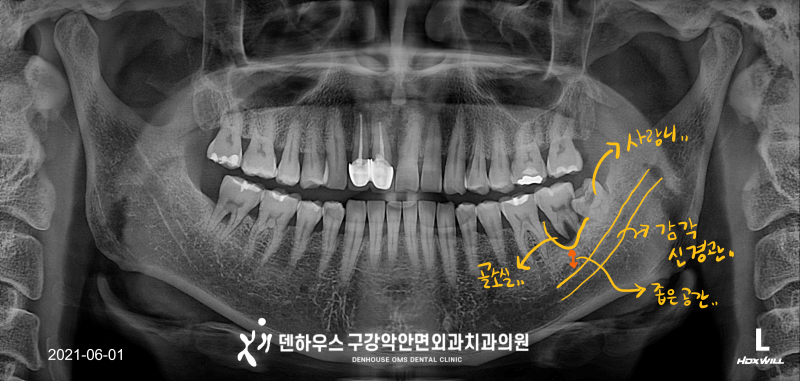

1. 임플란트 주위염 2. 매식체 문제 3. 보철물 문제 4. 기타 인천 용현동 치과에서 재수술을 해야 하는 경우는 다양합니다. 그 중 높은 비율을 차지하는 주위염은 시술 후 치아 주변에 형성되는 플라크가 제때 제거되지 않아 단단한 치석으로 굳어지게 되고, 그 위에 세균의 작용으로 염증이 생겨 통증을 동반하는 것입니다. 이는 치주질환과 비슷한 증상을 보이며 염증이 주변 조직을 파괴하여 인공 치근을 흔들고 심할 경우 탈락으로 이어질 수도 있습니다.임플란트 자체는 금속 재질이기 때문에 충치가 생기지는 않지만 원래 치아와는 달리 뿌리 부분이 더 얇기 때문에 머리와 뿌리 부분의 연결이 부드러운 곡선 형태가 아니어서 잇몸에 염증이 더 잘 생기게 됩니다.

이것은 원래 주위 잇몸 점막보다 혈관 분포가 적고 치주 인대와 같은 염증에 대응할 수 있는 세포가 적기 때문에 재생이 느리고 자연치주질환의 경우보다 빠르게 진행됩니다. 임플란트가 자연치아에 가깝게 대처할 수 있는 치료이기는 하지만 두 가지 가장 큰 차이점은 신경이 있는 것과 없는 것의 차이로 통증이 느껴지고 붓기로 인한 불편을 느껴 인천 용현동치과에 내원하시는 시기에는 이미 염증의 정도가 심하게 진행된 경우가 많습니다. 보이지 않는 이 질환, 어떤 단계로 진행되는지 알려드리겠습니다.

1. 음식물이 침전되고 치석과 치석이 쌓입니다.2. 치석 표면에 있는 세균이 잇몸 속으로 들어와서 염증을 유발합니다.3.심할 경우 잇몸뼈가 녹아 흔들리거나 치아탈락이 있을 수 있습니다.

-흡연- 허술한 구강-치주염- 강한 저기압-이 이 같은 다양한 원인으로 발생하는 주변염은 예방과 치료를 위한 다양한 방법이 있지만, 고민 개선에 의한 정기적인 관리 태만에서 발생하고 통계에 의하면 임플란트 시술을 한 사람의 약 80%가 주변 점막염을 가졌으며, 그 중 3분의 1이 주위 염에 진행합니다.주변 점막염의 경우 뼈까지 염증이 전이하지 말고 주변 점막에만 염증이 생긴 것으로 바로 치료하고 관리하면 잘 조절되는 부분인데, 이 단계를 넘어 주위염으로 진행하는 것으로 치료가 어려워집니다. 조기 발견 치료로는 비 외과적인 방법으로 비교적 쉽게 스케일링으로 치석 제거가 가능하지만, 염증이 심하면 잇몸 박리 소파 수술을 통해서 잇몸 절개 후에 염증을 제거하는 방법을 사용합니다. 그것보다 더 심한 임플란트가 흔들리거나 탈락한 경우 재수술을 하기도 합니다. 이 때는 염증으로 인한 바로 임플란트 식립이 불가능한 뼈 이식을 진행 뼈 이식 재료를 부족한 부분에 보강하고 뼈 융합 때문에 3~5개월의 시간이 걸리는 등 관리를 미루고 방치하면 더 길고 복잡한 치료 과정을 거쳐야 합니다.